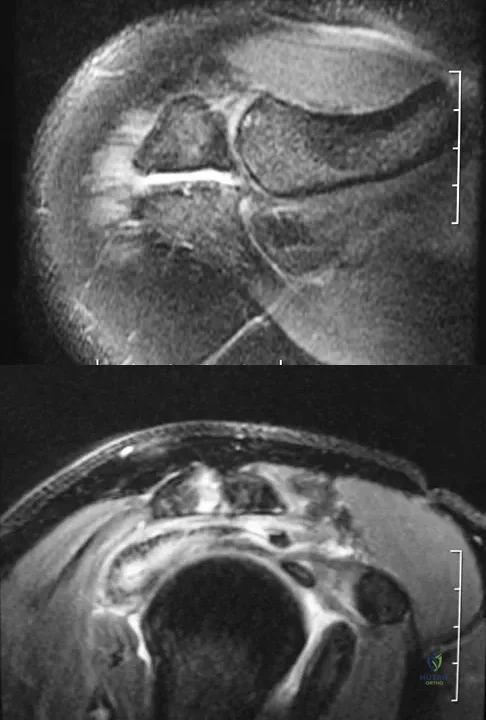

Figures 34a and 34b show the axial and sagittal MRI scans of a 36-year-old man who reports the insidious onset of pain in the right shoulder. What is the most appropriate description of the acromial morphology?

Explanation